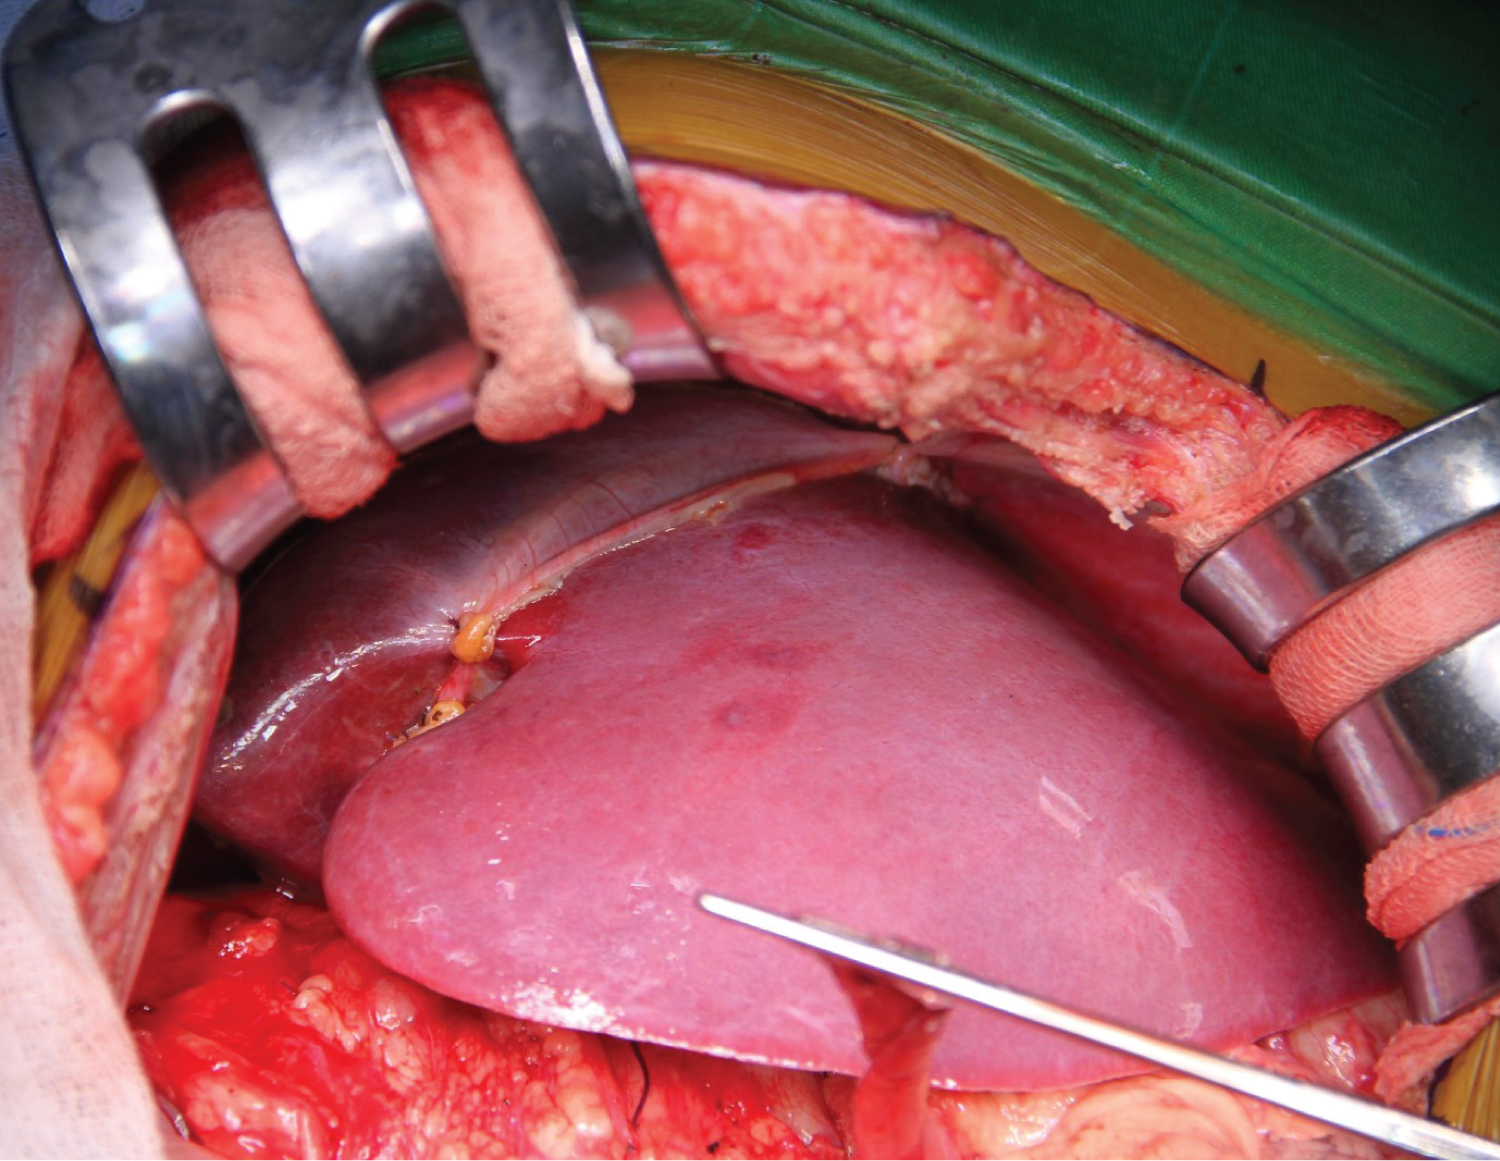

We aimed for mean arterial pressure (MAP) > 60 mmHg throughout the operation. 560g of liver tissue was removed from the patient (Figure 2). After the anastomoses of the great vessels were completed in the anhepatic phase of approximately 45 minutes, the clamp on the portal vein was removed, and reperfusion was achieved. The patient's blood pressure fell to 66/34 mmHg 2 minutes after reperfusion. The norepinephrine infusion dose was increased until his hemodynamics stabilized, and 5 mg of ephedrine and 100 mg of calcium chloride were given twice. In the intraoperative period, transesophageal echocardiography (TEE) provides invaluable information for closely monitoring pulmonary vascular resistance (PVR) and right ventricular functions in these patients. Since our patient had esophageal varices, we did not perform direct TEE, but when an extraordinary event occurred, we kept her at the patient's bedside to do it quickly. Our patient did not have pulmonary hypertension in the preoperative examination, and we tried to minimize the triggering factors that would increase PVR throughout the operation. We did not detect any increase in PVR in the measurement we made with PiCCO during the neo-hepatic phase. In the neo-hepatic phase, the dose of norepinephrine was reduced as the patient's hemodynamics returned to normal. Fluid therapy was performed considering the PiCCO parameters. The estimated blood loss during surgery was less than 250 mL. During the surgery, the patient was given a total of 1300 mL crystalloid, 1300 mL 5% albumin-containing colloid and 200 mL cell-caver, and 450 mL urine output was achieved. The inserted liver weighed 285g (Figure 3), and the operation continued for 7 hours. After the operation, she was taken to the intubated ICU and connected to a mechanical ventilator. While the patient was being followed on the ventilator, her SaO 2 was between 0.46 and 86-92%. On the 2 nd postoperative day, SaO 2 remained at 90-95%, hypoxemia resolved, weaning was applied, and the patient was weaned from the ventilator. After 2 days of oxygen support with a 2 L/min mask, she breathed in normal room air. After extubation, the patient's general condition and neurological examination were normal. Blood gas values, lactate level and hepatic transaminases returned to normal within days. Immunosuppressive drugs, steroids and nutritional support were administered to the patient. The patient was transferred to the service on the 4 th day after her follow-up in the ICU, and her follow-up continued. The patient was discharged 15 days after the operation without complications in the postoperative period.

Figure 2: 560g of liver tissue was removed from the patient.

Figure 3: The inserted liver weighed 285g.